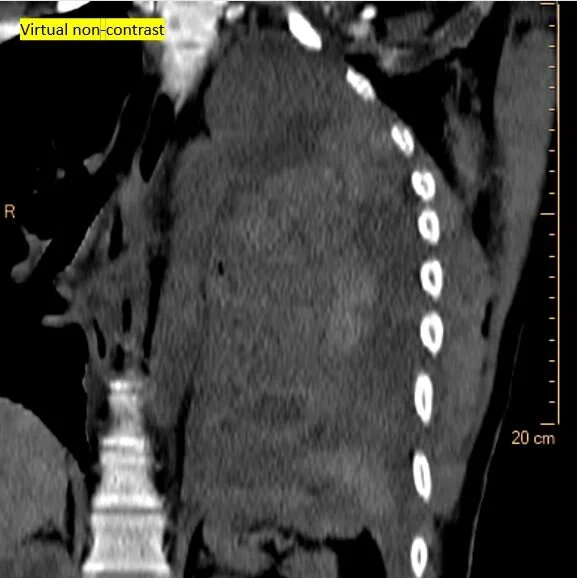

Virtual non-contrast shows clots surrounding the left lung